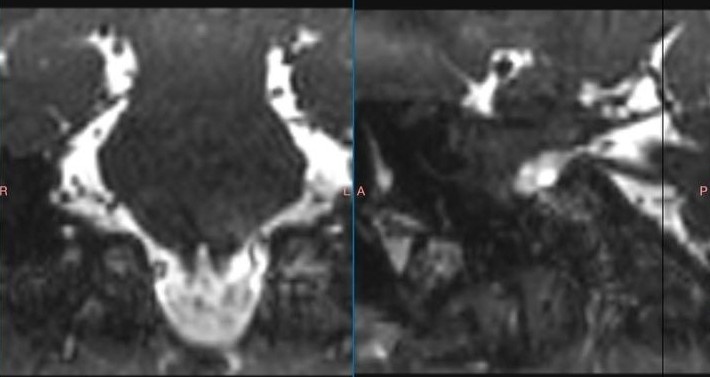

Сегодня с небольшими модификациями именно микроваскулярная декомпрессия является золотым стандартом лечения невралгии тройничного нерва, добавил министр. В основе теории возникновения болей лежит понятие нейроваскулярного конфликта — конфликта сдавления прилежащим сосудом корешка черепного нерва в месте его входа/выхода из ствола головного мозга.

Технически операция выглядит следующим образом. Делается небольшой разрез в заушной области на стороне поражения. Проводится мини-краниотомия, или трепанация. Тканесберегающая, максимальными размерами до двух сантиметров. Осуществляется подход к структурам мостомозжечкового угла под микроскопом. Врач видит сосуд, чаще всего артериальный. Видит зону нейроваскулярного конфликта. Разъединяет спайки, укладывает специальный инертный материал и устраняет компрессию.